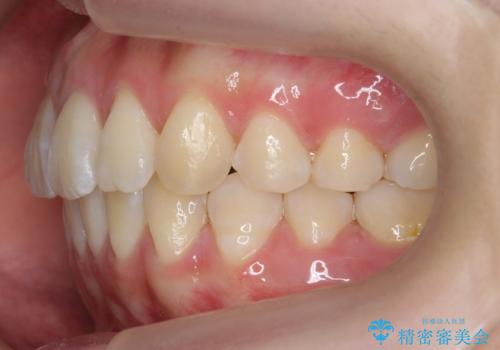

出っ歯 軽度のがたつき インビザラインで

- 奥歯を後ろに下げる処置をおこなっています。

前歯にオープンバイト気味の症状がありましたが、前歯を後ろに下げることでしっかりかませています。

前歯のずれも治り、しっかり下がりました。

前歯を下げるのに、顎間ゴムを使用していただいています。